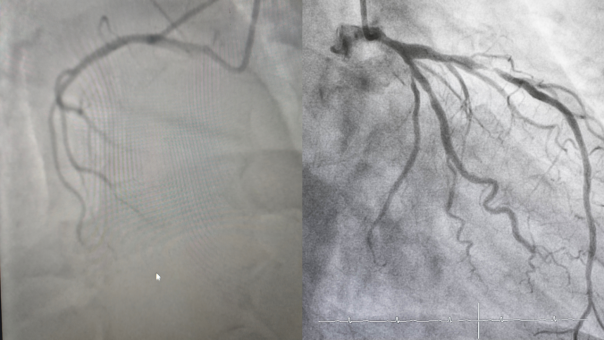

二、冠脉CTA:心脏血管的无创高清筛查

河南省中西医结合医院医学影像科团队介绍,冠脉CTA全称冠状动脉CT血管造影,是一种无创、快捷的心脏血管检查。通过静脉注射对比剂,经CT扫描及三维重建,可清晰显示心脏血管的立体图像。整个检查仅需10—15分钟,门诊即可完成,无需住院、无需插管,安全便捷。

冠脉CTA检查主要作用:判断冠状动脉有无狭窄及狭窄程度;识别斑块性质,区分相对稳定的钙化斑块与易破裂的高危软斑块;排查冠脉先天畸形;评估支架或搭桥术后血管通畅情况。

三、冠脉CTA与冠脉造影,如何选择?

冠脉CTA属于无创筛查,适合中低危人群初步排查,费用较低,结果正常基本可排除冠心病。

冠脉造影属于有创检查,是诊断冠心病的“金标准”,可同时进行支架治疗,适合症状典型、高度怀疑严重血管病变者。

简单原则:无症状或症状不典型,先做冠脉CTA;症状典型、疑似心梗,直接做冠脉造影。